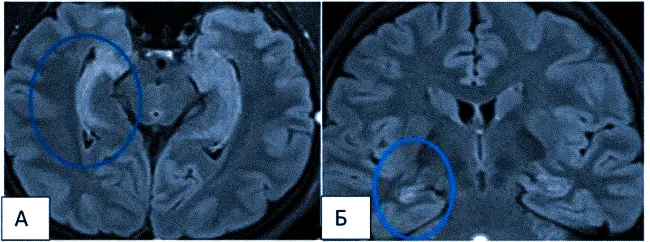

- склероз гиппокампа — наиболее распространенное структурное изменение мозга у пациентов с фармакорезистентной эпилепсией; характеризуется уменьшением объема гиппокампа, повышением сигнала на T2-взвешенных изображениях и нарушением внутренней структуры. Операции на височной доле у таких пациентов в 2/3 случаев приводят к исчезновению приступов с потерей сознания.

Рис. 4. МР-томограмма пациента с левосторонним склерозом гиппокампа (коронарные и аксиальные срезы).